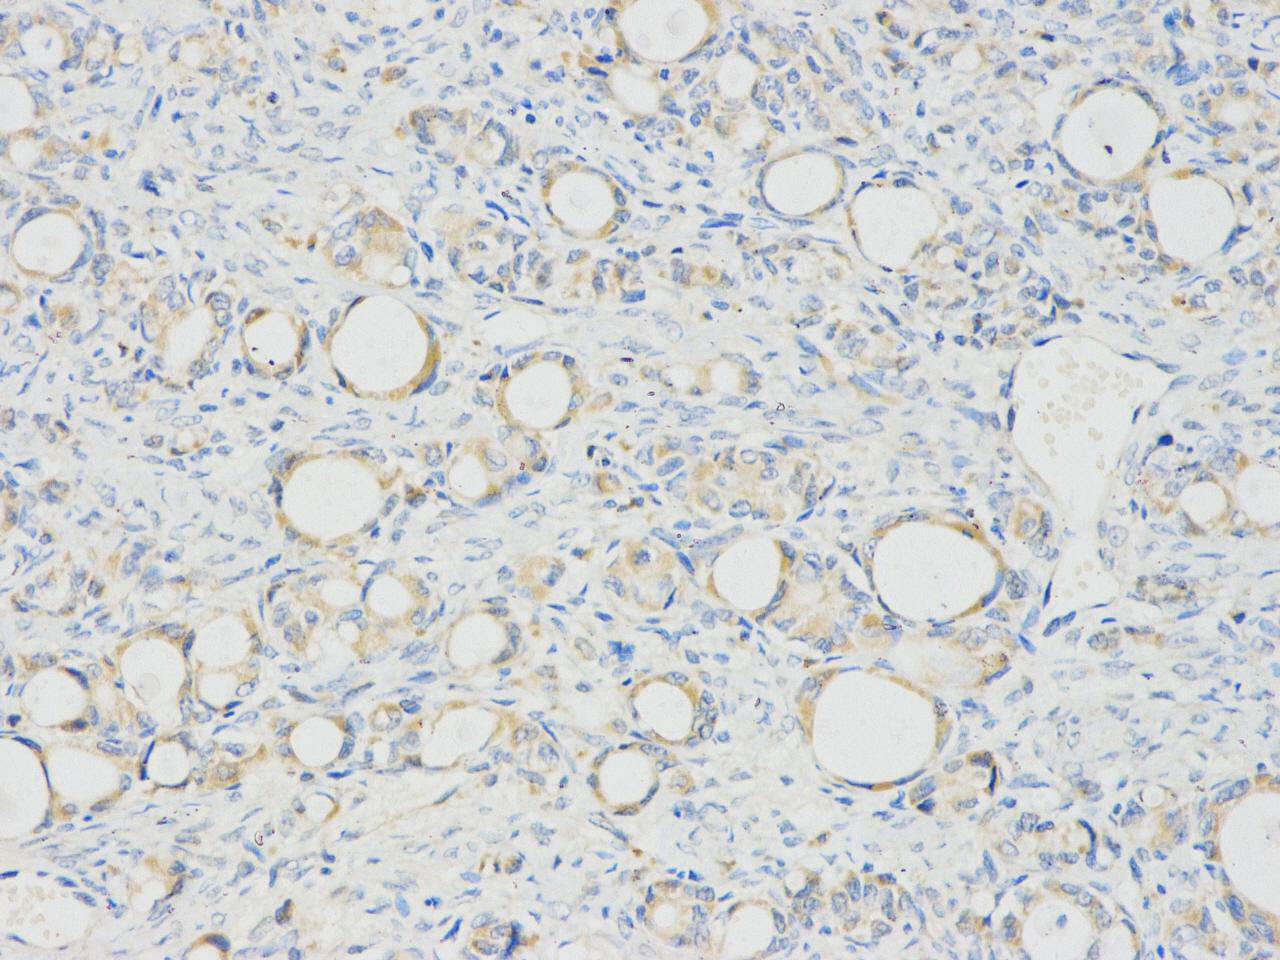

Immunohistochemical analysis of paraffin-embedded human ovary tissue using anti-nucleolin rabbit polyclonal antibody.